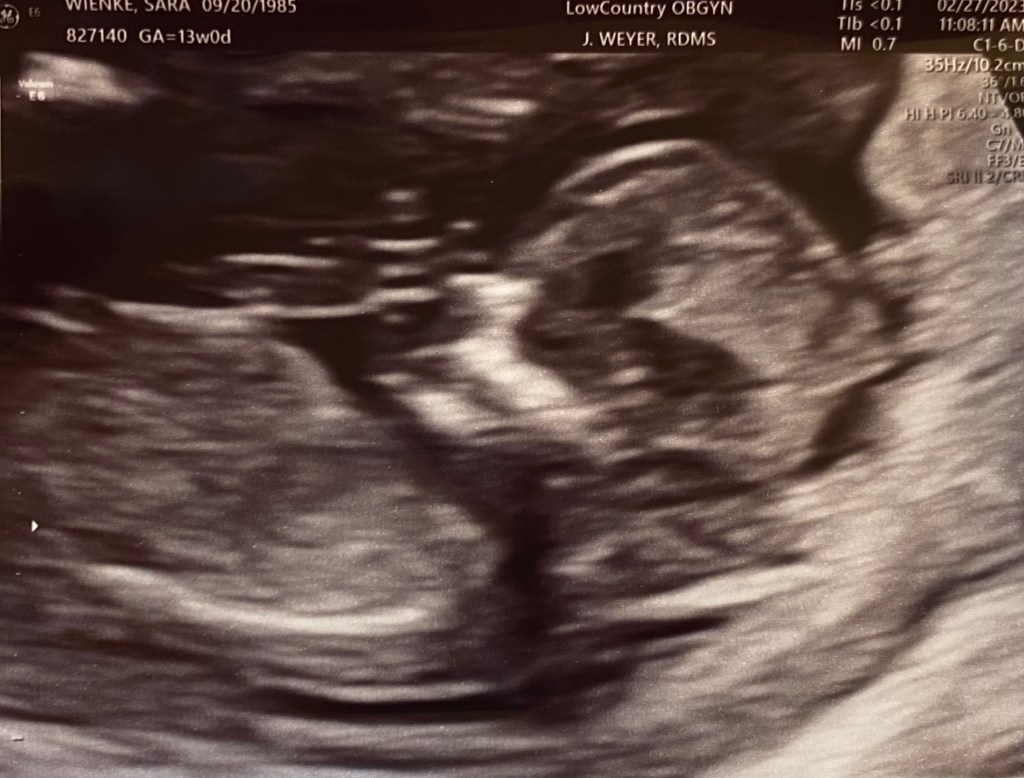

My fourth child, Sadie, will also not enter this world. We found out a few weeks ago that our fourth pregnancy, a very loved and wanted pregnancy, was a little girl and she had Down syndrome. At 12 weeks of pregnancy, a genetic counselor called to give me the results of our NIPT test. I knew that was bad news and already had an instinct that our baby was a girl with Down Syndrome, I’m not sure how I knew. I avoided the call. I called back once I felt ready for this news. She told me that the NIPT came back with a high risk for Trisomy 21 (Down Syndrome). A genetic counselor by training myself, I knew what this meant but I did not practice after NIPT came to market ~10 years ago. I asked her “how high is the risk?” and she said 90%. Oof. That hit my heart like a dagger. I asked her if she could tell me the gender. She checked and said “it’s a female fetus.” And the dagger twisted. I cried and thanked her for the information. She said that they could see us for an ultrasound that afternoon or a CVS in the morning at the downtown office. I was thankful I had chosen to go to the high risk clinic from day 1. Having chosen a high deductible insurance plan allows me the flexibility to refer myself and had been seeing a midwife there I liked quite a bit but there were always MFMs there when needed. I told her I wasn’t sure what to do. I called my husband for the next 20 minutes and he did not answer. I cancelled my afternoon meetings and drove home. I woke him from our 4yo bed as they were slumbering together. I pulled him into our bedroom so Calvin wouldn’t hear and I told him what I had learned. We cried together. My mother came over and we went straight to the office for the ultrasound. I asked the genetic counselor to review everything with my husband, then we went to look at baby. I could see it as soon as the ultrasound tech did. The space behind the babies’ neck was larger than it should be. Normal is less than 3mm but most healthy kids are around 1-1.5 (as were Calvin and Conor’s). Sadies’ NT (nuchal translucency) was 4.85mm and I could see that it extended the length of her back. I sobbed. Chris cried in response to my distress. We got some pictures of our sweet girl before the MFM came in to tell us the findings. She looks great except for a cystic hygroma, a hallmark of Down Syndrome. With that information, the risk Sadie has Down syndrome is now 99%. A CVS, a diagnostic test, is invasive and would give us ‘conclusive’ information. I say that in quotes because that is also a test with 98-99% accuracy where there are some exceptions to the rule and the babies chromosomes don’t always match the placental chromosomes (both NIPT and CVS are sampling placental derived chromosomes). Having seen a traumatic CVS when I was a student, I declined, feeling comfortable that the ultrasound had given us the information we needed to confirm the diagnosis that NIPT had identified.